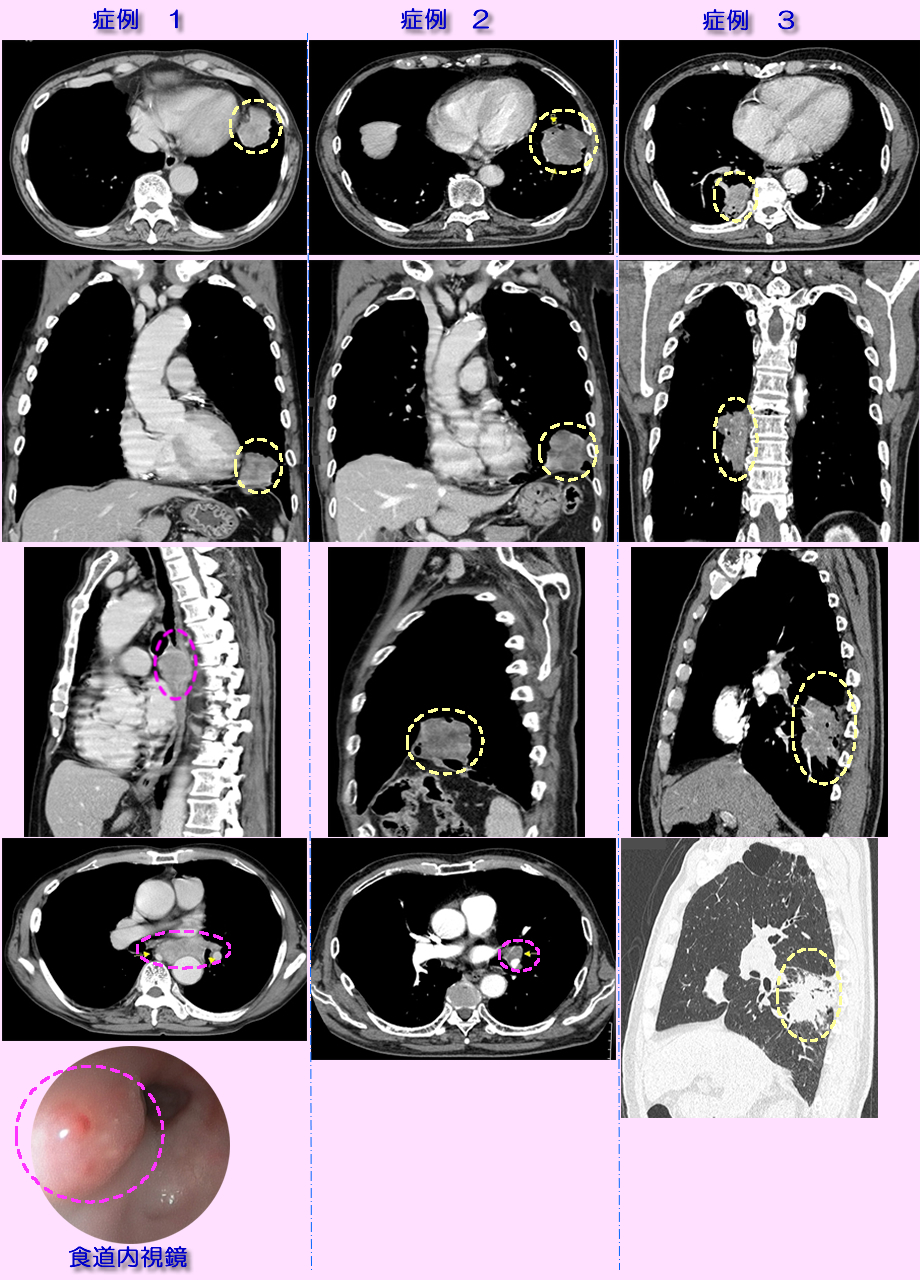

| 症状 | 掲載症例1は1ヶ月以上続く咳と嚥下時の痛みで来院、症例2は軽い胸部痛で受診、症例3は背部痛で受診 |

| 診断 | 画像診断には胸部X線撮影、詳細な診断にはCT、MDCT、PET-CTなどを用います。腫瘍の組織性状(がんの種類)の確定には喀痰の細胞診、気管支鏡を用いた腫瘍部位の生検、経胸壁的な穿刺針生検などが行われます。下記掲載画像は3次元的な任意断面画像が得られるMDCTにるものです。腫瘍の性状(血管発達状況)推定や、肺血管と腫瘍の区別、位置関係を明瞭にするため造影剤使用下に撮影したもです。黄色の破線内ががんの部位です。がんの種類は生検、血液腫瘍マーカから扁平上皮がんでした。がんの縦隔部位や肺門リンパ節への転移を適切な画像断面から評価します。その転移の有無、広がり部位から、手術の可能性、放射線治療か抗がん剤唖治療か、その併用かなどの治療方針を判断します。ピンクの破線で囲む部位に縦隔、リンパ節への転移を認めます。症例1は縦隔部位へ転移したがんは食道を圧迫し、大動脈周囲にも浸潤しており、食道内視鏡検査(最下段の画像)ではがんが食道内に膨隆して圧迫し、浅い潰瘍を生じています。嚥下時の胸の痛みや食物停滞感の原因が理解されます。本例は手術不能で放射線・化学療法が行われました。症例2もピンンクの楕円で示す部位にリンパ節転移を認めます。症例3は放射線療法が開始され3ヶ月後、他界されました。 |

| 治療 | 肺癌の種類(細胞・組織性状)とがんの広がり程度(転移、周囲への浸潤)、年齢などから、手術、放射線療法、化学療法(抗がん剤)治療などを選択します。 |